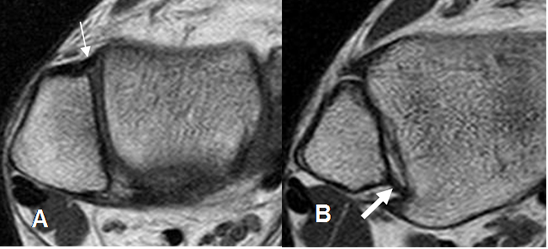

Fig 10. Ligamento peroneoastragalino anterior normal.

A: RM axial en T1 y B: RM coronal en T2.

Fig 11. Ligamento peroneoastragalino posterior normal.

A: RM axial en T1 y B: RM coronal en T1.